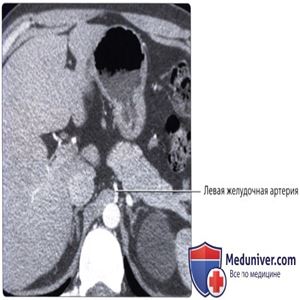

Ангиография чревного ствола, артериальная фаза: определяются только общая печеночная и селезеночная артерии, берущие начало от чревного ствола. У этого пациента левая желудочная артерия имеет обособленное начало от аорты, что показано на последующих КТ срезах.

КТ с контрастированием, аксиальный срез: на срезе через верхний отдел брюшной полости визуализируются левая желудочная артерия, начинающаяся обособленно от аорты, а не обычное начало от чревного ствола.